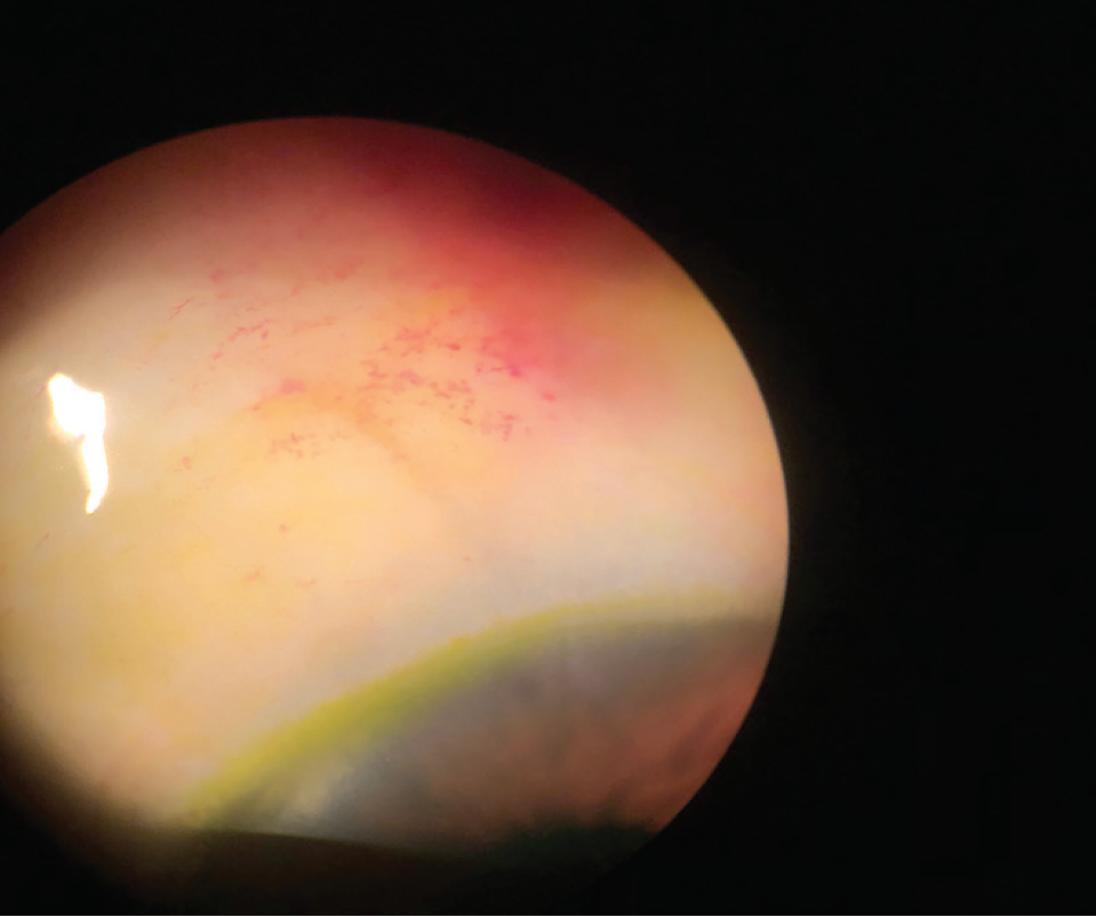

One week after surgery. The bleb is diffuse, conjuctival vessels have Bleb Dysesthesia Fam:bleb dysesthesia can occur due to the presence of a large nasal bleb in the palpebral fissure, which causes an uneven distribution of. Successful treatment of the bleb leak, hypotony, or bleb dysesthesia was defined as resolution of the hypotony, the leak, or both, and adequate. Normally as we blink, the eyelids spread the tears smoothly over the corneal surface.. Bleb Dysesthesia.